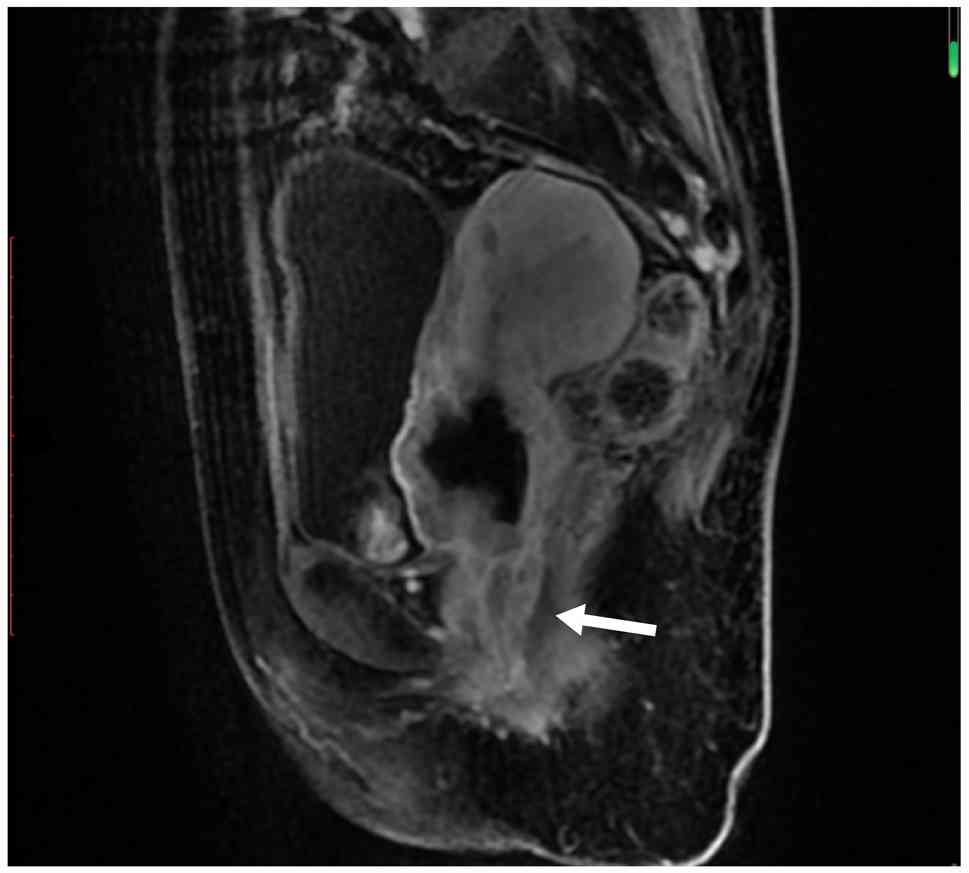

Examples of MRI diagnostic images from multiple patients are shown in Fig. 1, Fig. 2, Fig. 3, Fig. 4, Fig. 5. Fig. 1 shows an irregular soft-tissue mass in the cervical region, clearly visible on the axial sequence of T2-weighted fat-saturated imaging. The mass may suggest cervical lesions or tumors. Fig. 2 displays multiple lymph node metastases in the pelvic region on the axial sequence of DWI. The high-signal areas indicate that the lymph nodes might be affected by tumor metastasis. Fig. 3 reveals an irregular soft-tissue mass in the cervical region on the sagittal sequence of T2-weighted fat-saturated imaging. The mass is shown to have extended into the vaginal area, with the sagittal view aiding in the assessment of the lesion's longitudinal extent. Fig. 4 displays an irregular soft-tissue mass in the cervical region on T1-weighted enhanced imaging. The mass shows significant heterogeneous enhancement, suggesting that the lesion may be malignant. Fig. 5 illustrates a lesion in the cervical and vaginal regions on the sagittal sequence of T1-weighted enhanced imaging. The lesion area demonstrates heterogeneous enhancement, further indicating the possibility of a malignant tumor.

T1-weighted enhanced sagittal sequence

showing heterogeneous enhancement of the lesions (white arrow) in

the cervical and vaginal regions.

Figure 5.

T1-weighted enhanced sagittal sequence showing heterogeneous enhancement of the lesions (white arrow) in the cervical and vaginal regions.